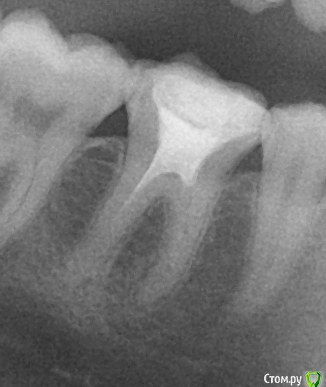

1. Прошу подсказать что на снимке, сломанный инструмент? пломбирования каналов не делалось, там может быть только материал для депофореза, но он вроде не может быть таким яркобелым как металл.

после 2 сеансов депофореза

http://s41.radikal.ru/i093/1710/58/3e2739c62d30t.jpg

Да, есть небольшой фрагмент инструмента в ближнем корне зуба.

2. Если сломан инструмент, как я понимаю шансы на успешное лечение гораздо меньше? и зуб может теперь гораздо чаще обостряться?

И да и нет, вероятность успеха действительно чуть меньше, но поскольку отлом произошел не в самом начале лечения а в процессе, то шансы на успех все равно достаточно высокие.

Если все хорошо пролечено зуб не должен обостряться ни чаще ни реже, он должен перестать вас беспокоить.

Самое худшее что делает отломок, невозможность полной обработки канала. но отлом маленького фрагмента инструмента в апикальной части - это достаточно безобидно, т.к. канала дальше и нет. В вашем случае требуется тщательная обработка всех каналов, пломбировка и наблюдение. Потом при необходимости можно сделать резекцию верхушки корня.